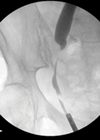

Case 1 What does this plain X-ray of kidneys, ureters and bladder (KUB) show? What, according to the 2009 The National Institute for Health and Care Excellence (NICE) guidelines, is the most appropriate first-line treatment? What factors do the NICE...

Case 1 What does this x-ray of the kidney, ureter and bladder (KUB) show? What are the likely causes? What is the pathology behind medullary sponge kidneys (MSK)? What is the risk of urolithiasis with MSK? How are such patients...